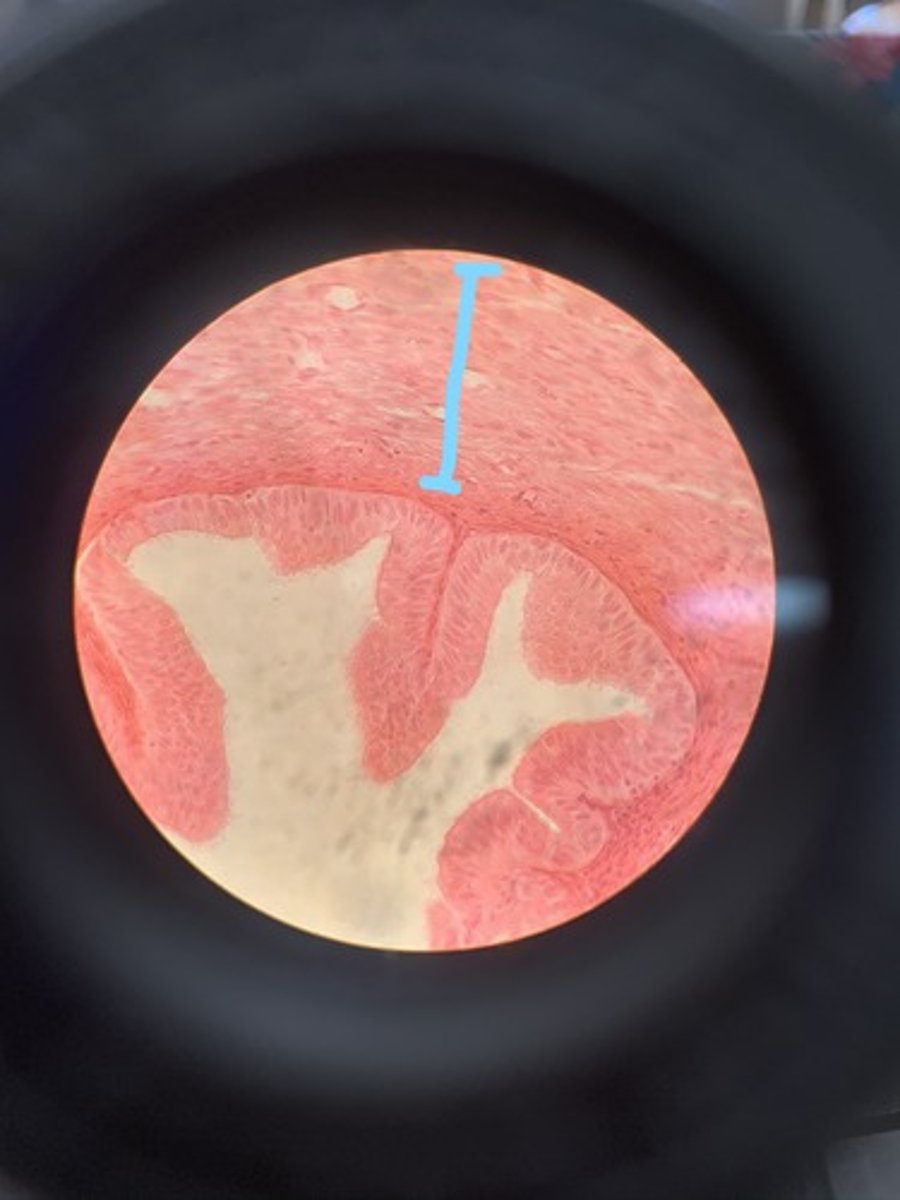

uterus

endometrium

myometrium

perimetrium

cervix

uterine glands

basal layer

in endometrium

functional layer

smooth muscle

in myometrium it is made of

farthest layer

loose connective tissue, and simple squamous epithelium